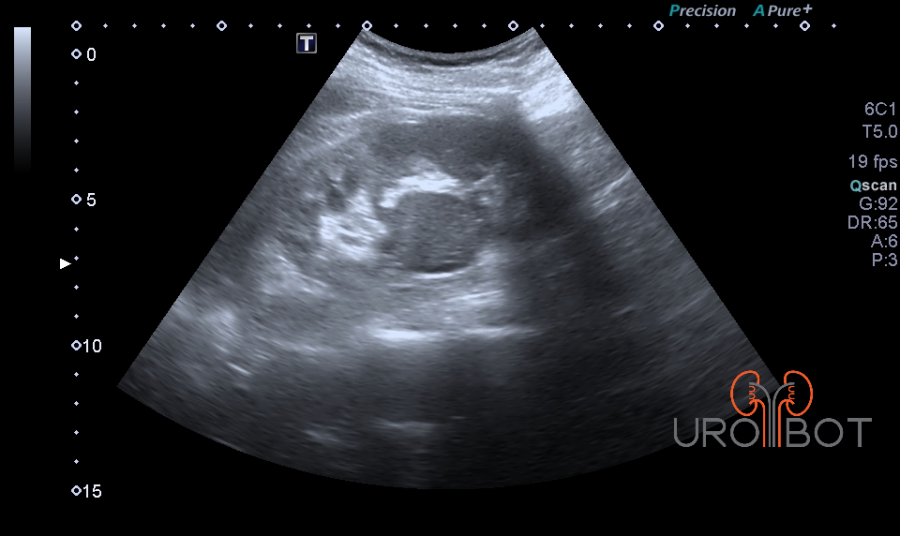

In der Früherkennung ist der Ultraschall die führende Untersuchung. Ab einer Größe von 2 cm kann man bereits bösartige Tumore von gutartigen Zysten unterscheiden. Doch obwohl die Qualität der heutigen Ultraschallgeräte stark zugenommen hat, wird man zu weiteren Unterscheidung und Klassifizierung radiologische Verfahren wie die CT (Computertomographie) oder aber die MRT (Magnetresonanztomographie) einsetzen.

Das Video zeigt eine sonographische Untersuchung der rechen Seite mit Nachweis eines großen Tumorthrombus in der unteren Hohlvene.